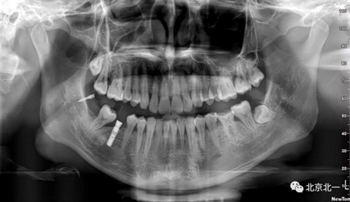

術(shù)后拍片。

正畸支抗直立47

第一次支抗釘脫落, 第二次支抗釘位于48位置, 頰側(cè)舌側(cè)舌側(cè)扣牽引。